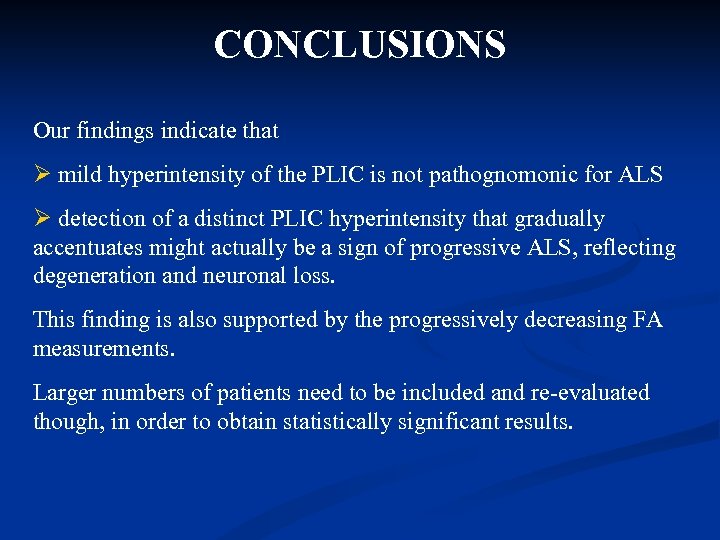

CONCLUSIONS Our findings indicate that mild hyperintensity of the PLIC is not pathognomonic for ALS detection of a distinct PLIC hyperintensity that gradually accentuates might actually be a sign of progressive ALS, reflecting degeneration and neuronal loss. This finding is also supported by the progressively decreasing FA measurements. Larger numbers of patients need to be included and re-evaluated though, in order to obtain statistically significant results.

CONCLUSIONS Our findings indicate that mild hyperintensity of the PLIC is not pathognomonic for ALS detection of a distinct PLIC hyperintensity that gradually accentuates might actually be a sign of progressive ALS, reflecting degeneration and neuronal loss. This finding is also supported by the progressively decreasing FA measurements. Larger numbers of patients need to be included and re-evaluated though, in order to obtain statistically significant results.